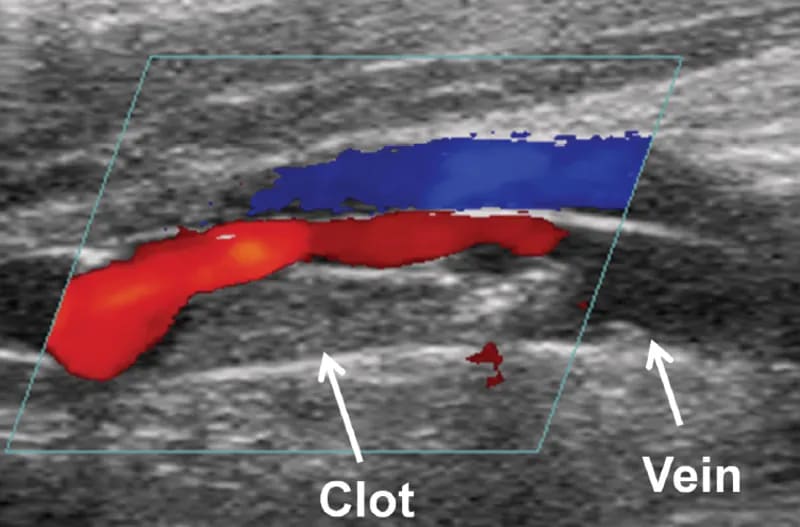

What is a DVT Doppler Ultrasound?

A Deep Vein Thrombosis (DVT) Doppler Ultrasound is a special type of ultrasound which is used to measure blood flow through the upper limb veins as well as the deep leg veins and assess any blockage to blood flow such as a blood clot. DVT commonly occurs in calf veins, and occasionally in those of the thigh.

When isolated in the leg veins, DVT can result in pain, skin inflammation and ulceration. However, if the clot breaks off and travels through the bloodstream into the lungs, it is known as pulmonary embolus which can be life-threatening.